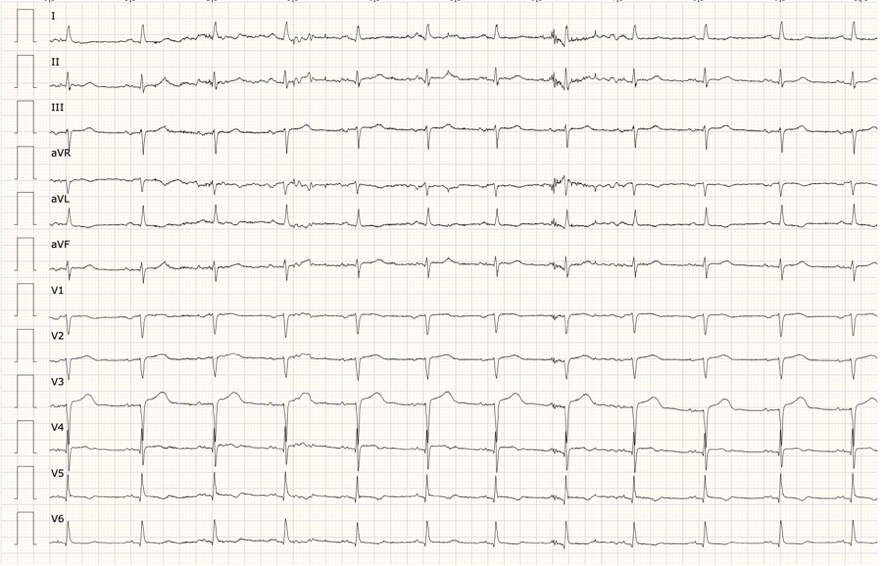

A las 24 horas del ingreso el ECG mostró ondas T negativas profundas generalidas y QT largo.

En nuestro caso clínico no se encontraron desencadenantes claros para el cuadro clínico. El ECG mostró cambios evolutivos típicos de esta entidad con T negativas profundas en precordiales y alargamiento del QTc hasta 600ms (ver imagen 3). Se mantuvo ingresada monitorizada sin presentar eventos arrítmicos ni insuficiencia cardiaca descompensada. A los 6 días del ingreso presentó recuperación completa de la función ventricular normalizándose la ecocardiografía y parcialmente el ECG (QTc normal, mantenía T negativas poco profundas en V4-V6). El séptimo día de ingreso fue dada de alta.